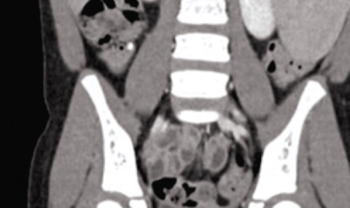

A 6-year-old female with history of previously resolved iron-deficiency anemia presents to the emergency department (ED) for numerous episodes of nonbloody, nonbilious vomiting and diffuse abdominal pain that began on the day of presentation. She had initially presented to her pediatrician who felt a large left-upper-quadrant abdominal mass and referred her to the ED for further evaluation. She has no associated diarrhea or urinary symptoms. What's the diagnosis?